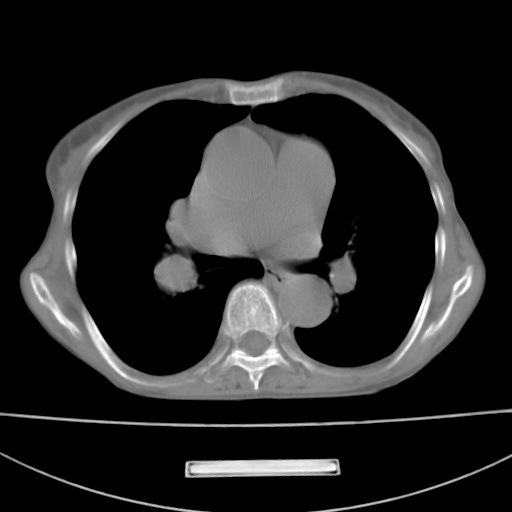

患者 女 67岁,反复咳嗽咳痰2年,加重伴喘及双下肢浮肿1月

陈旧性肺结核、慢性支气管炎、支气管扩张症、肺心症、肺动脉高压。

诸大血管及f肺门血管增粗迂曲.左下肺多发薄壁空腔影.部分非也透亮度增高.薄曾扫描可区分肺气肿类型.考虑1.慢性支气管炎 2.左下肺支气管扩张 3.肺气肿 4 肺动脉高压5.是否有先心病病史

支扩,肺动脉高压